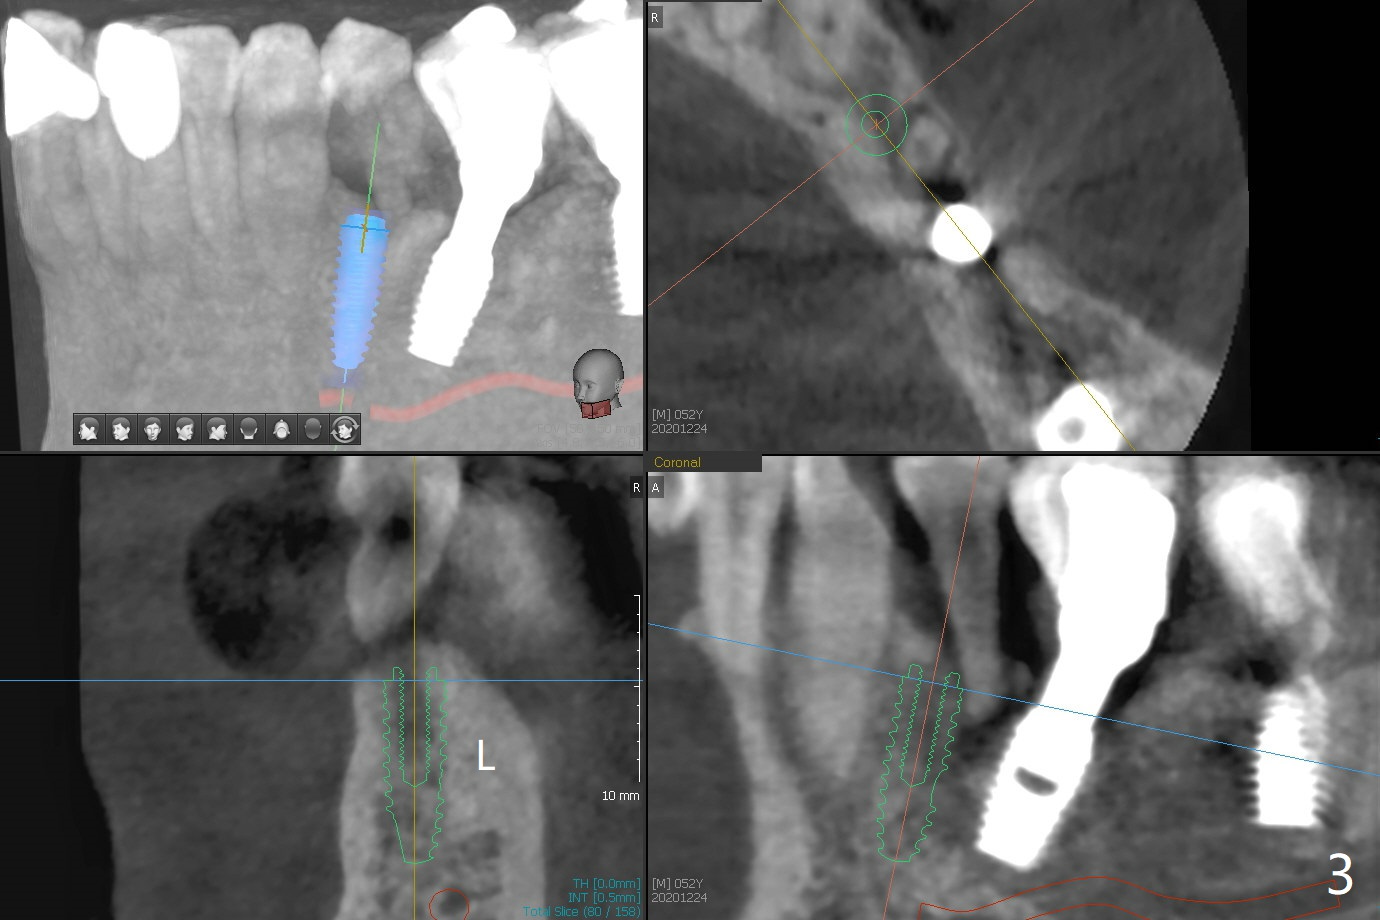

52岁男右下4植体脱落,植骨后,使用左侧咀嚼,发现左下4松动(图一,二),无法吃饭,认为必须拔除植牙(图三,四),徒手种植的邻近植体位置不好,但无骨质吸收(图五,六(牙冠粘固后9年10月)),4种植必须用导板